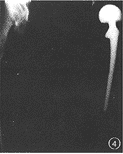

例4男,40岁,股骨颈骨折后股骨头缺血性坏死。行人工股骨头置换术,术后疼痛。X线片示人工股骨头前倾位置入。术中测量假体前倾45°(图4)。

图1男,72岁,右全髋关节置换术后5年。右股骨假体内翻下沉,假体远端骨水泥断裂,髋臼假体周围有连续的透亮区图2女,65岁,人工股骨头置换术后5年。髋臼内壁磨损,容积性骨缺损图3女,68岁,右侧人工股骨头置换术。假体外翻位,假体柄自内侧骨皮质穿出图4男,40岁,股骨颈骨折后股骨头缺血性坏死。行人工股骨头置换术,人工股骨头过度前倾位置入图5男,67岁,左侧全髋关节置换术后7年。假体股骨柄断裂,股骨假体近端内翻,骨水泥周围透亮区形成图6男,62岁,左侧全髋关节置换术后4年。髋臼假体金属杯与聚乙烯内衬脱位,髋臼金属假体与股骨假体直接接触